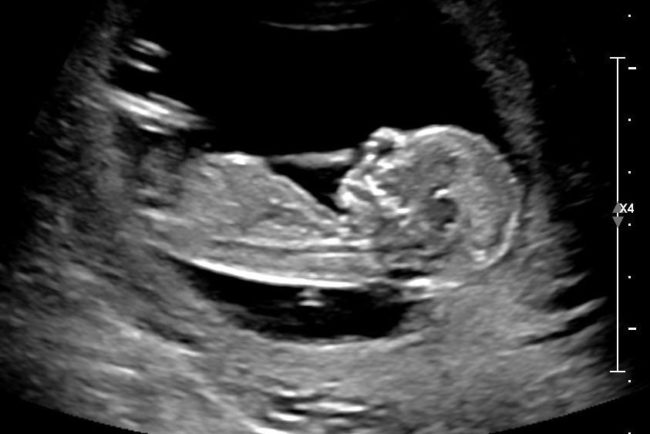

Quando uma mulher descobre que eu perdi um bebê durante a vigésima semana de gestação, normalmente elas se abrem sobre suas perdas, mas reduzem a significância de suas perdas dizendo que elas estavam “somente” de seis semanas, oito semanas, ou x semanas grávidas quando ocorreu a perda. Elas normalmente seguem após o “somente” dizendo algo…